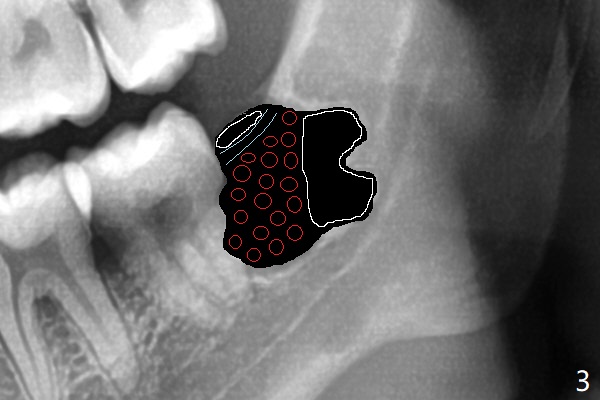

A 22-year-old man agrees with extraction of #16 and 17 with bone graft in the latter socket (Fig.1). Because of horizontal impaction, the mesial root tip (Fig.1' *) overlaps with the Inferior Alveolar Canal. 5x5 cm CT will be taken with special bite block to show the ramus as posterior as possible (internal and external oblique ridges). Since the crown of the 3rd molar seems to be buccal to the distal portion of the 2nd molar, the anterior oblique incision should be placed as mesial as possible (Fig.2 red line). After extraction, collagen plug (Fig.3 large white area) will be inserted into the root sockets, while sticky bone (circles) in the coronal socket. The latter will be covered by 2 pieces of PRF membrane, followed by compressed Osteogen Plug (small white area, tp be visible in the postop panoramic 2 bitewings).